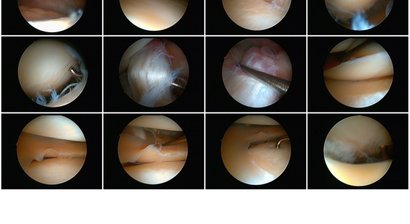

Arthroskopie (Knie, Schulter)

Die Arthroskopie ist ein minimal-invasives Untersuchungs- und Behandlungsverfahren, welches es ermöglicht größere Gelenke genauer zu untersuchen und dabei etwaige Schäden an den Gelenkstrukturen zu beheben. Die arthroskopische Untersuchung ist in vielen Fällen ein besonders...

Häufige Gründe für eine Kniearthroskopie sind degenerative Veränderungen am Gelenk, entzündliche Veränderungen sowie traumatisch bedingte Veränderungen und Verletzungen. Zu den Anwendungsgebieten der Arthroskopie im Bereich vom Knie zählen u.a.: Meniskusrisse...